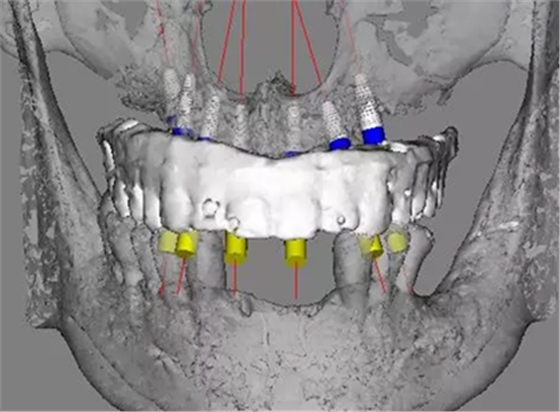

治療計劃及種植方案設(shè)計

患者骨高度嚴(yán)重不足,尤其是后牙區(qū),骨高度基本都只有2mm。按常規(guī)傾斜植入的方式也不可行,因此選擇在5號位通過內(nèi)提升方式植入植體。